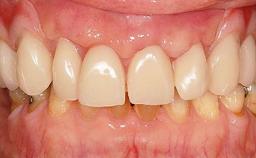

Immediate Implant Placement and Immediate Provisionalization with a Prefabricated-Shell Provisional Crown

In this case, Arndt Happe describes how he achieved a stable outcome at 5 years by giving careful attention to the coronal aspect of the transmucosal area of the provisional, creating a slim emergence profile.

A healthy 31-year-old female patient presented with a failing maxillary left lateral incisor crown. The crown regularly loosened, and the remaining tooth was neither restorable nor rational to treat. The patient had a high smile line, a medium soft tissue biotype with a compromised mesial papilla (shorter than the contralateral one), and a horizontal scar in the buccal soft tissue as a result of past periapical surgery.

Gingival display at full smile High

Gingival Phenotype Medium-scalloped, medium-thick